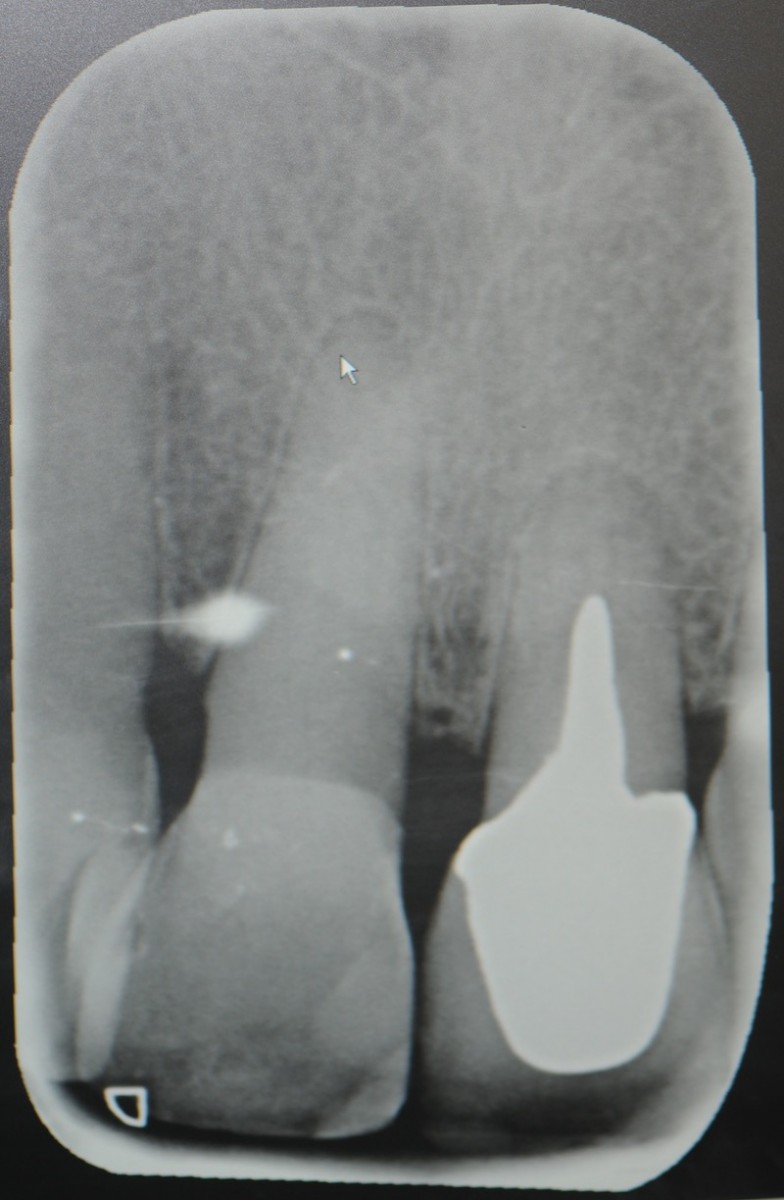

The objective of this prospective cohort study is to test the performance of a new xenogenic collagen matrix as a socket sealing material, to allow second-intention healing of post-extractive sockets filled with a xenogenic bone substitute or with an immediate submerged implant.

10 patients were recruited, presenting a single-rooted tooth scheduled for extraction. After atraumatic tooth removal, the post-extractive alveolus received either a socket preservation procedure or an immediate submerged implant. In both cases, the gingival margins of the alveolus were sealed with a xenogenic collagen matrix (Mucoderm, Botiss Dental, Zossen, Germany). The following parameters were evaluated: